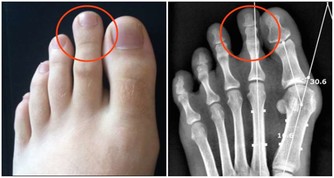

中醫有一句話:“筋軟一寸,壽增十年”人身上筋很多,研究發現,腳部的筋越軟,人就越長壽!

如何把腳部的筋變軟呢?一是雙腳互打,二是揉腳筋,揉腳筋要重點揉腳底上的地筋。

● 道醫通過內觀內證發現:人的筋之根就在腳部,治病要治根,養生也要調根。因此只拉身體的筋,而不把腳部的筋拉開,是治標不治本!